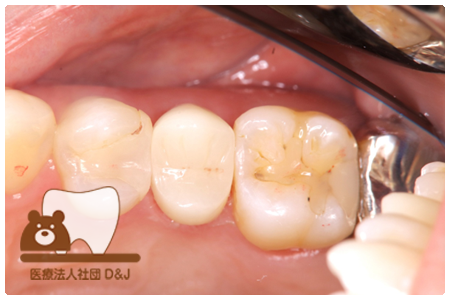

症例4フルジルコニアクラウン 左下6

治療前

治療後

37歳 男性

- 治療内容

- 以前のクラウンがセメントの劣化により外れた為その上にフルジルコニア製の被せ物を装着しました。見た目と強度を両立した自由診療の治療です。

- 治療期間

- 1カ月

- 費用

- 自費

フルジルコニアクラウン:77,000円(税込)

(R8.1月時点)

- その他の治療の費用は含まれておりません。

- リスク・副作用

- 硬い素材のため、かみ合う歯に負担がかかることがあります。将来取り外す場合に歯に負担がかかることがあります。強い力が加わると、まれに欠けたり割れたりすることがあります。